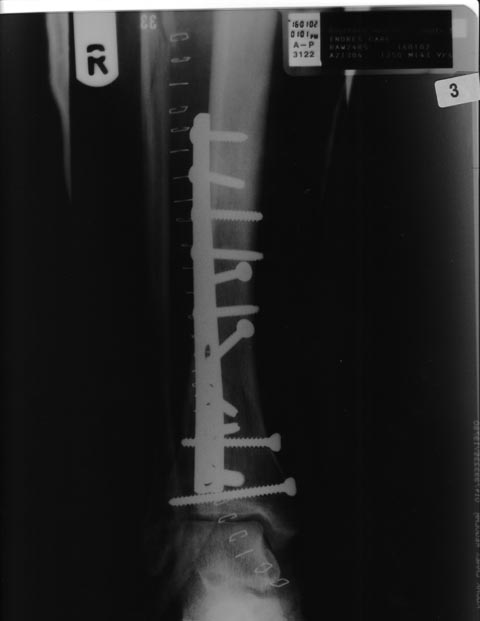

Our boss broke his leg while white water rafting during Eco Seagate 2002. He had to have numerous pins inserted into it. Here's his X-ray.